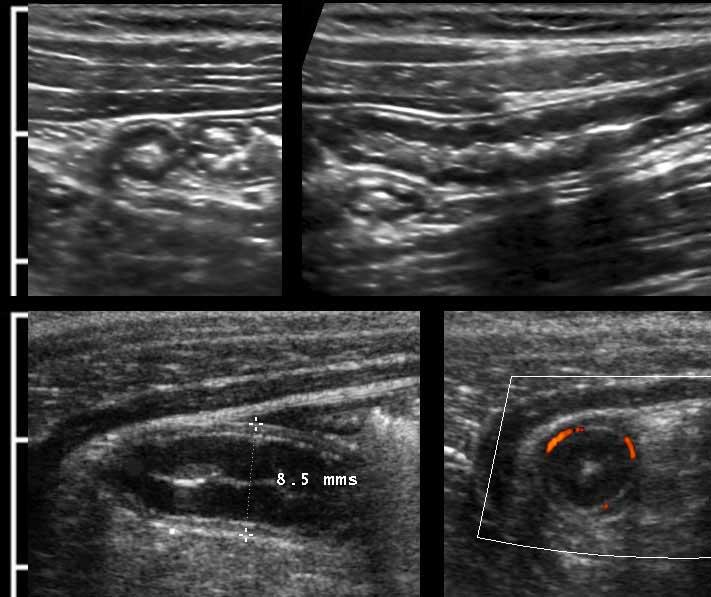

Đo độ dày thành ruột bằng siêu âm là khó khăn vì độ dày thay đổi theo các chuyển động nhu động ruột.

Ở cá nhân này, các số đo trong mặt phẳng dọc (hình trên) và trong mặt phẳng ngang khi ép nhẹ (hình dưới bên trái) có sự biến thiên đáng kể, nhưng khi ép vừa phải (hình dưới bên phải) các số đo có độ tái lập tốt và chính xác.

Vì lớp thanh mạc tăng âm mỏng hiếm khi có thể nhìn thấy rõ, độ dày thành ruột được đo từ bờ ngoài của lớp cơ mặt bụng đến bờ ngoài của lớp cơ mặt lưng, và sau đó tất nhiên, chia đôi.

Thông thường, độ dày thành ruột non đơn lớp khi ép là khoảng 1,5 – 2,5 mm.

Đường kính ngoài của ruột thừa được đo theo cách tương tự như ruột: trong quá trình ép vừa phải từ bờ ngoài của lớp cơ thành bụng trước đến bờ ngoài của lớp cơ thành bụng sau.

Được đo như vậy, đường kính của ruột thừa bình thường này (trái) là 4,5 mm và của ruột thừa viêm này (phải) là 8,5 mm.

Trong nhiều sách giáo khoa, giá trị ngưỡng cắt được báo cáo là 6 mm, tuy nhiên đây không phải là giá trị đáng tin cậy.

Rettenbacher (Radiology 2001; 218: 757-62) đã thực hiện một nghiên cứu lớn và phát hiện rằng đường kính của ruột thừa bình thường từ 6 mm trở lên chiếm 27% các trường hợp, với khoảng dao động từ 2-13 mm.